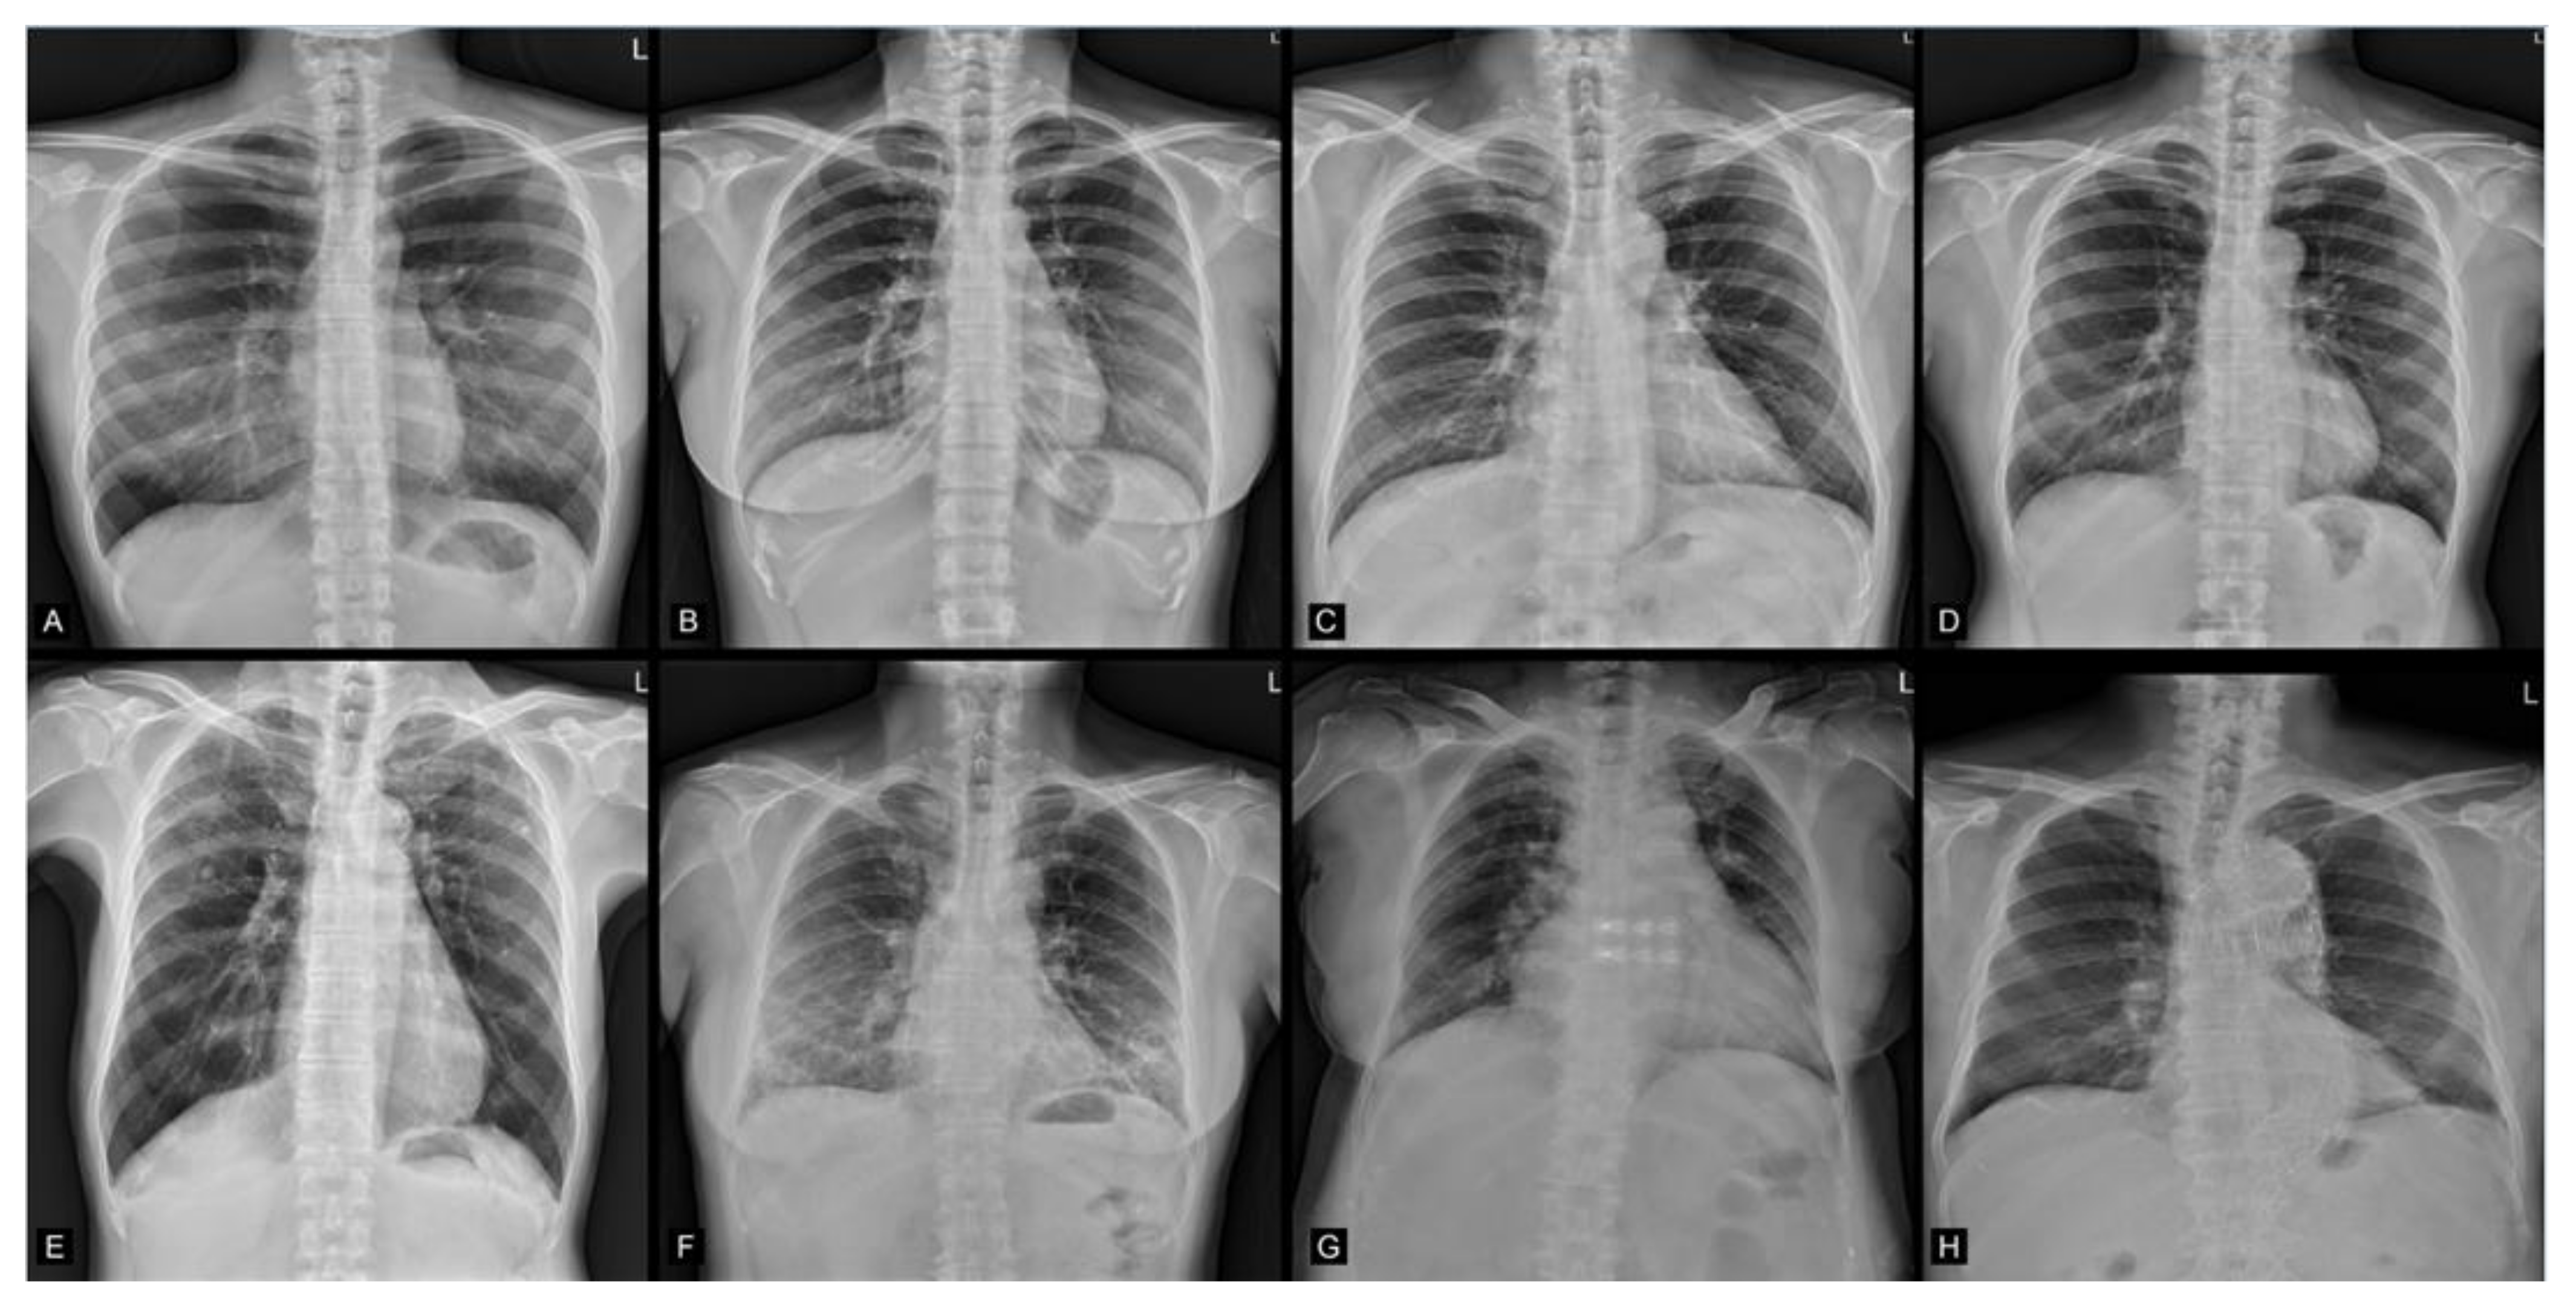

2.2. Image Data Acquisition

3. Results